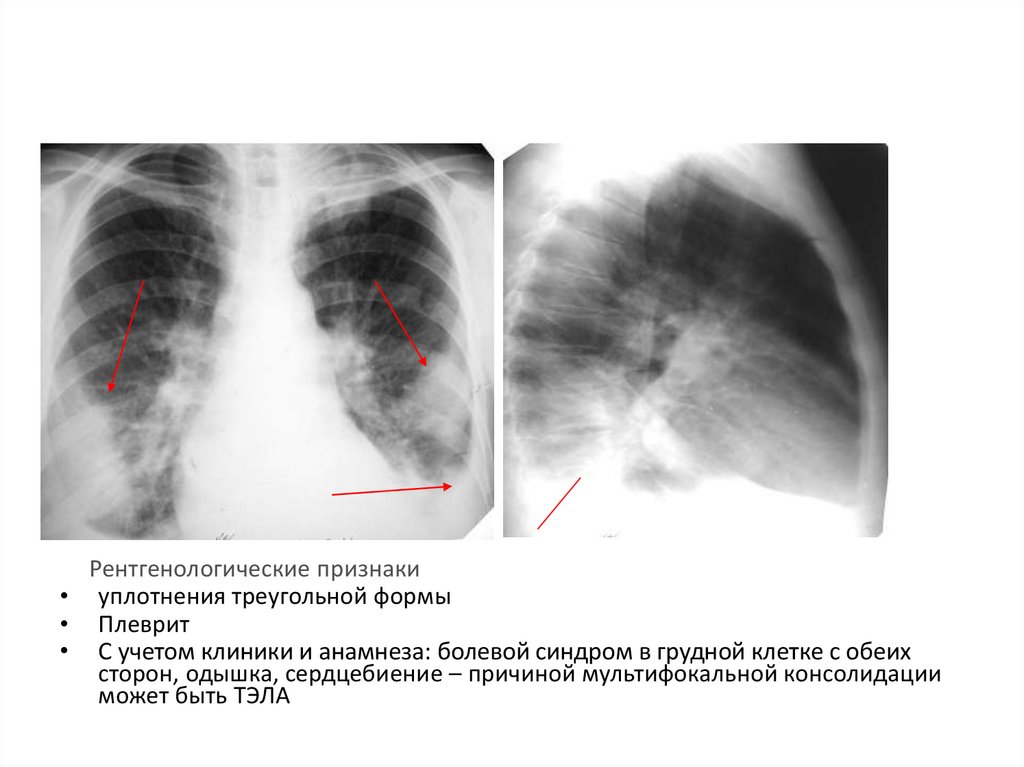

Ячеистая деформация легочного рисунка: медицинская визуализация